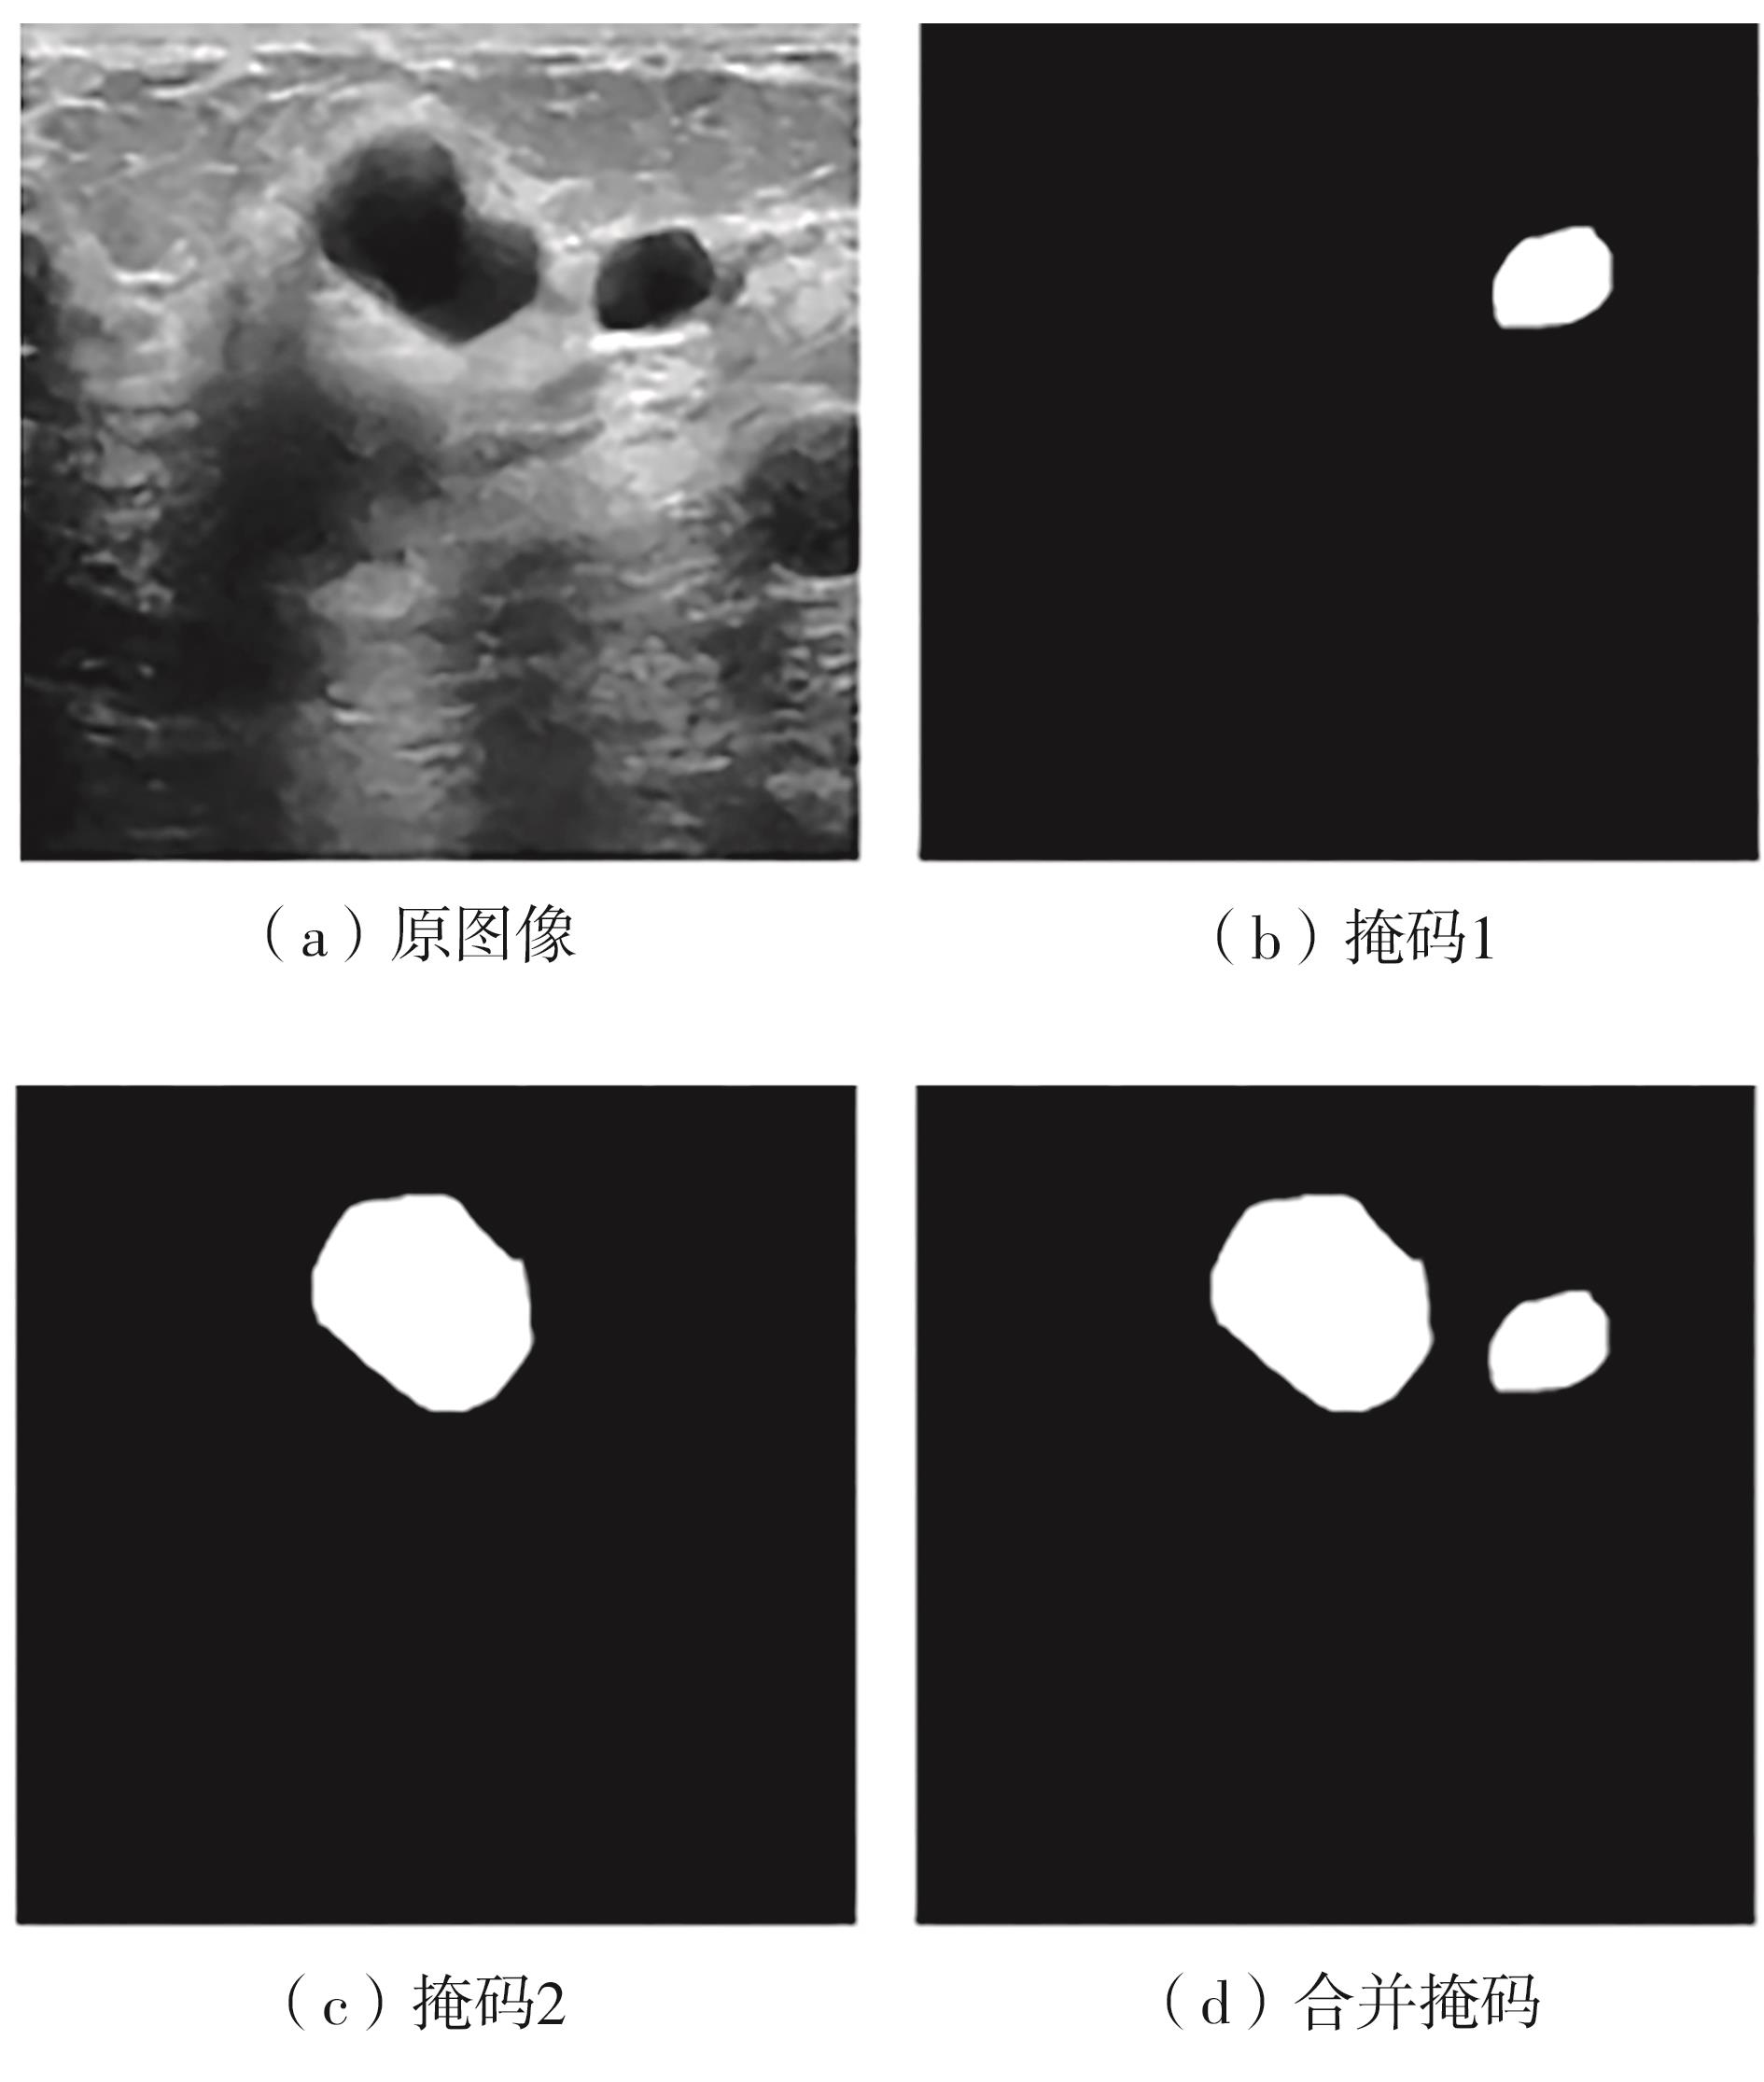

乳腺癌是全球女性最常见的恶性肿瘤之一,准确的病变分割对于乳腺癌的早期诊断与治疗具有重要意义。然而,由于病变形态的多样性以及超声成像机制的复杂性,现有基于深度学习的乳腺超声图像病变分割方法在分割准确性方面仍面临巨大挑战。为进一步提升乳腺超声图像中病变区域的分割精度,该文基于经典U-Net架构,提出了一种新型乳腺超声图像病变分割网络(CWSASKM-BBAM-Net)。首先,在网络中引入逐通道空间自适应选择核卷积模块(CWSASKM),根据不同通道的语义特征为每个空间位置自适应选择感受野大小,以增强多尺度信息的建模能力;然后,引入双向边界感知机制(BBAM),通过融合正向与反向注意力,对目标显著区域及其边界进行协同建模,同时逐步提升对非显著区域与病变区域的区分能力,以进一步强化边界信息的表达;最后,在3组公开乳腺超声图像数据集(BUSI、UDIAT和STU)上开展分割实验。结果表明:该方法在数据集BUSI上的杰卡德指数、精确率、召回率和Dice相似系数分别为71.97%、82.85%、81.40%和80.44%,较次优方法分别提升1.69、1.05、1.28和1.84个百分点;在数据集UDIAT上,这4项指标分别达到78.14%、88.31%、86.73%和86.10%,较次优方法分别提升了2.75、2.04、0.56和2.01个百分点;在外部数据集STU上,该方法也取得了优于其他方法的整体表现。实验结果表明,CWSASKM-BBAM-Net在乳腺超声图像分割任务中展现出更优的整体性能。